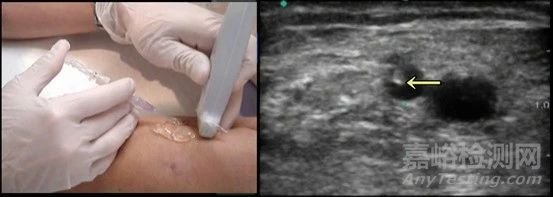

IVUS是通過(guò)導(dǎo)管技術(shù)將微型超聲探頭送入血管腔內(nèi),通過(guò)超聲波掃描和反射,從而提供在體血管腔內(nèi)影像,其能清晰顯示管壁結(jié)構(gòu)的厚度、管腔大小和形狀等,精確地測(cè)量血管腔徑及截面積,甚至可以辨認(rèn)鈣化、纖維化和脂質(zhì)池等病變。因此,IVUS可為術(shù)者進(jìn)一步介入治療提供依據(jù),達(dá)到精選支架、精準(zhǔn)療效的目的。

血管內(nèi)超聲在冠脈精準(zhǔn)介入中發(fā)揮著至關(guān)重要的作用。它能夠?qū)崟r(shí)顯示血管的截面圖像,為醫(yī)生提供了極為詳細(xì)的血管內(nèi)部情況。通過(guò)高分辨率的成像,醫(yī)生可以清晰地辨認(rèn)鈣化、纖維化和脂質(zhì)池等病變。據(jù)相關(guān)研究顯示,在對(duì)冠心病患者的檢查中,血管內(nèi)超聲能夠發(fā)現(xiàn)約 30% 的冠狀動(dòng)脈造影無(wú)法顯示的早期動(dòng)脈粥樣硬化病變。對(duì)于冠狀動(dòng)脈造影顯示的臨界病變,血管內(nèi)超聲可以進(jìn)行精確定量分析,精確地測(cè)量血管腔徑及截面積,甚至可以辨認(rèn)鈣化、纖維化和脂質(zhì)池等病變的大小和程度。